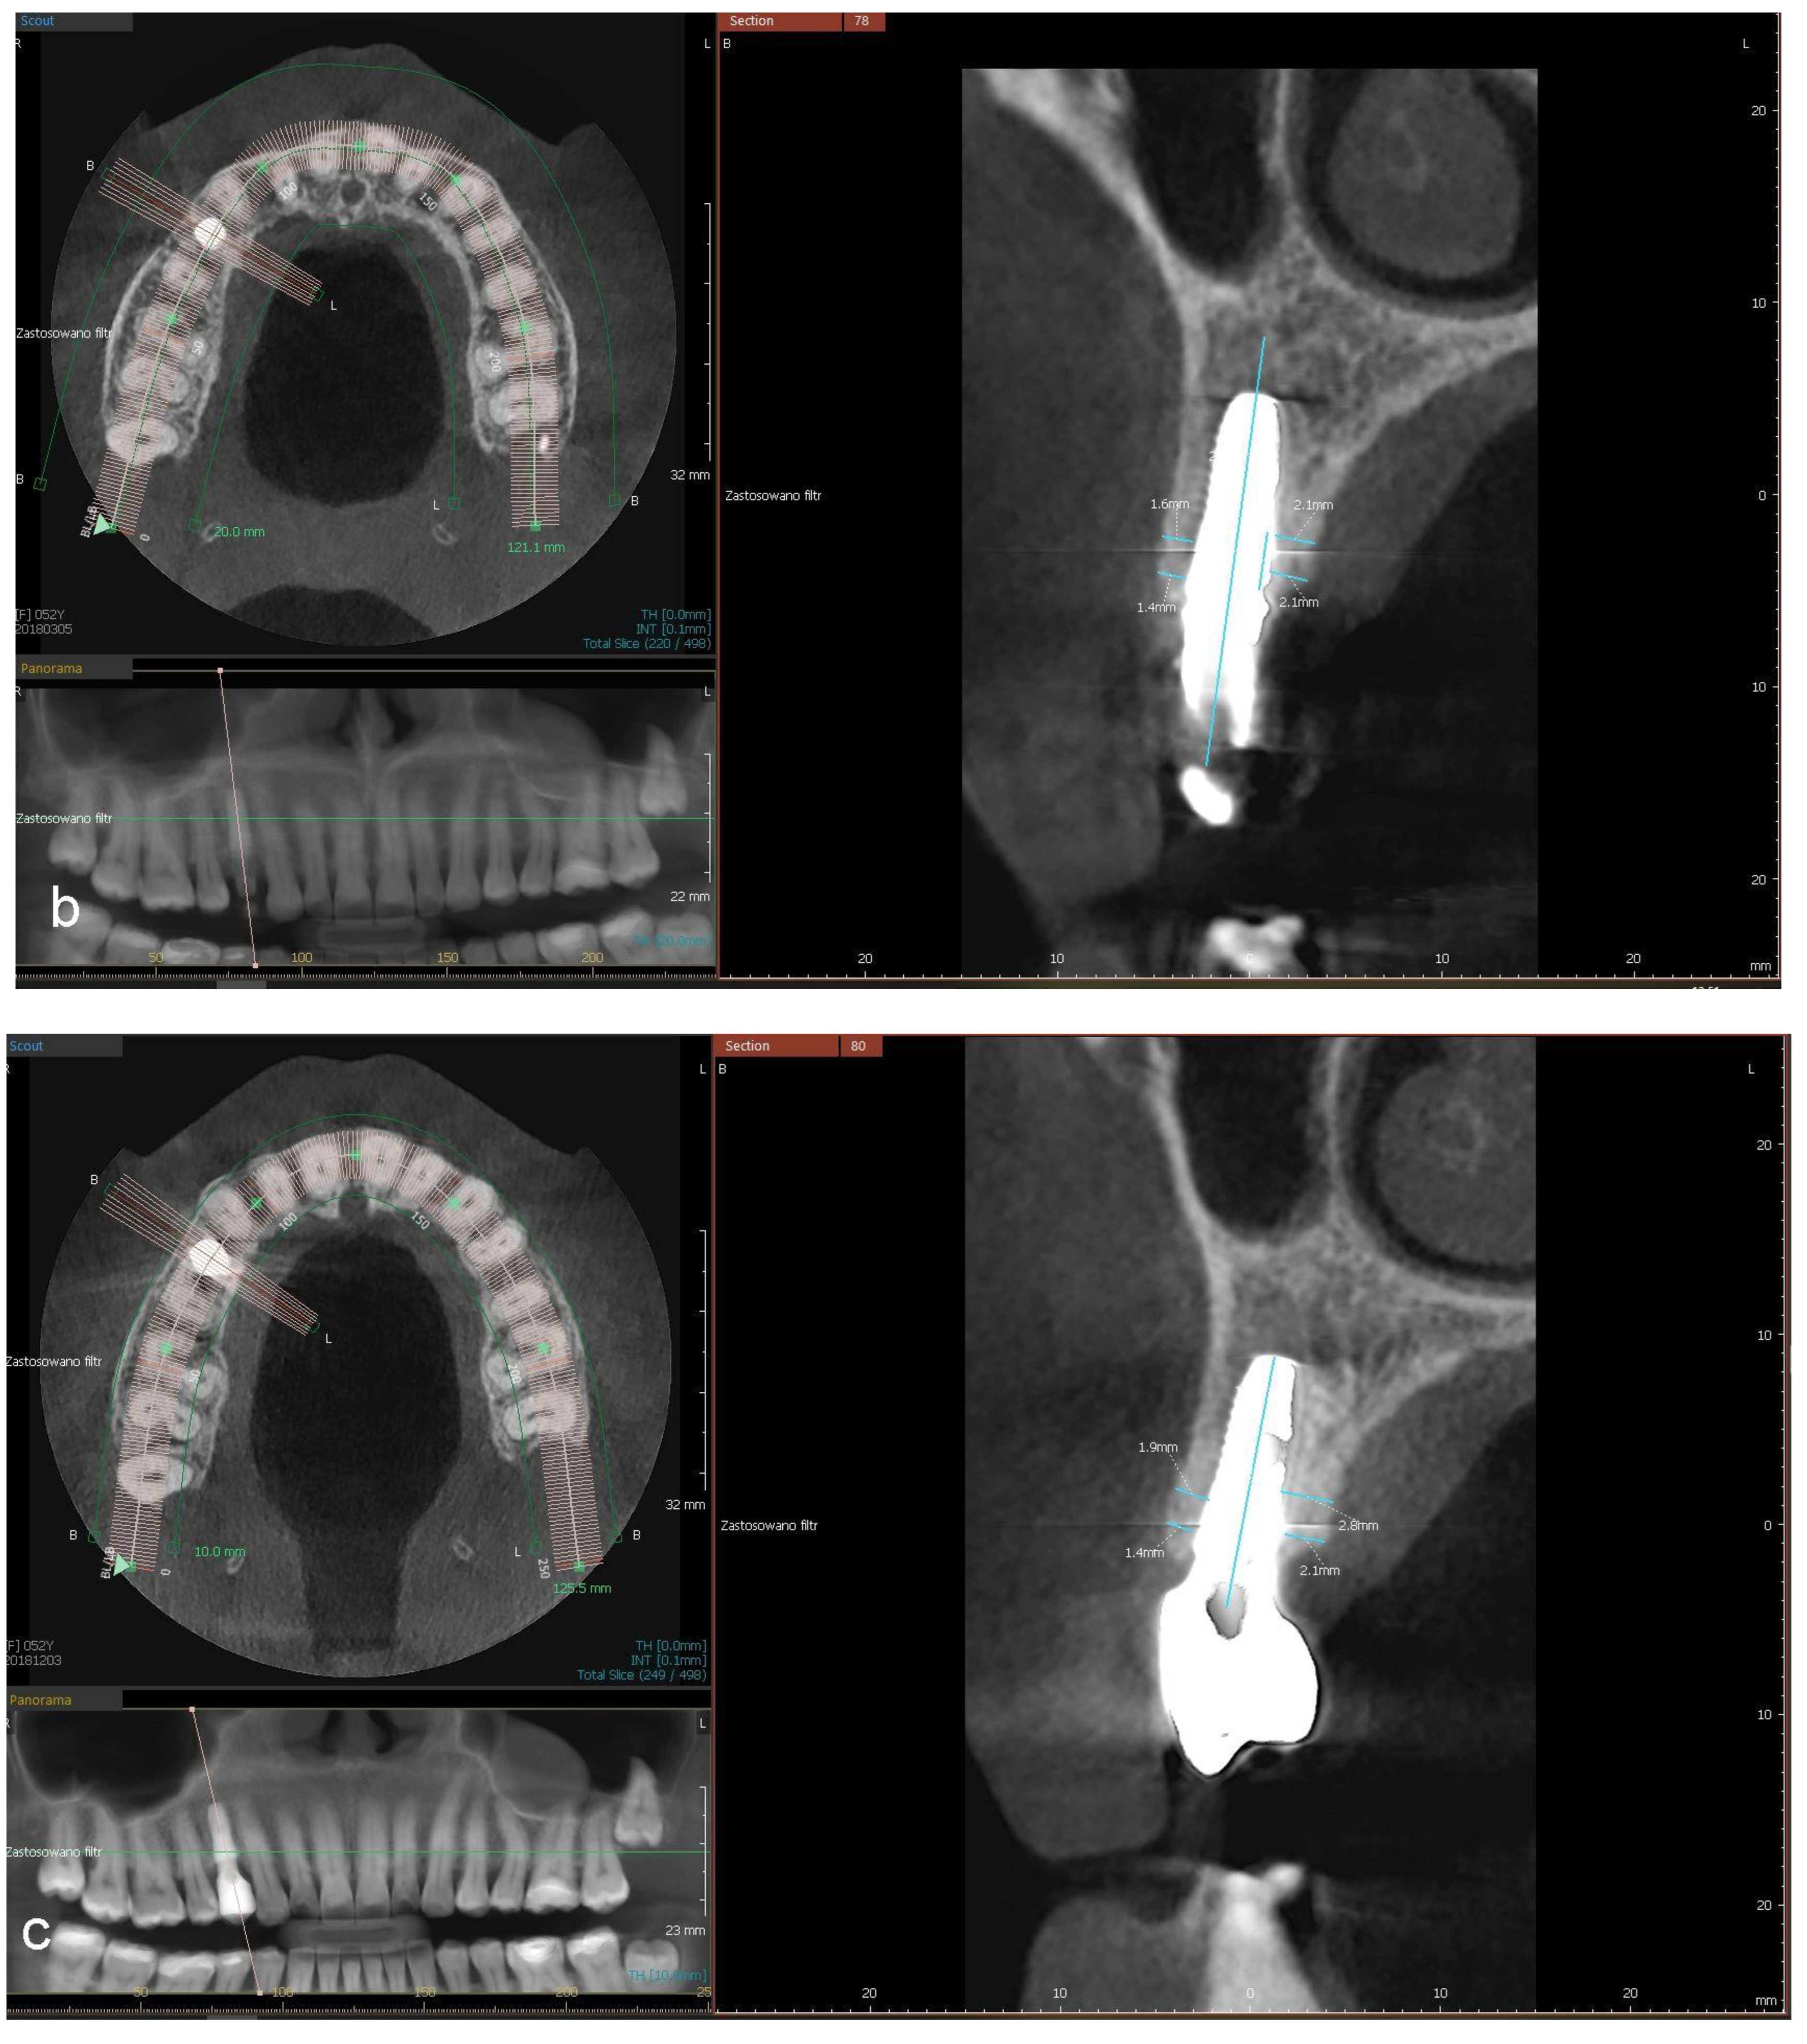

- a distance between the implant’s platform and buccal and palatal/lingual bone margin (dehiscence)

- thickness of buccal and palatal/lingual plates, 1 mm and 3 mm apically from the implant’s platform (perpendicular to the long axis of the implant).